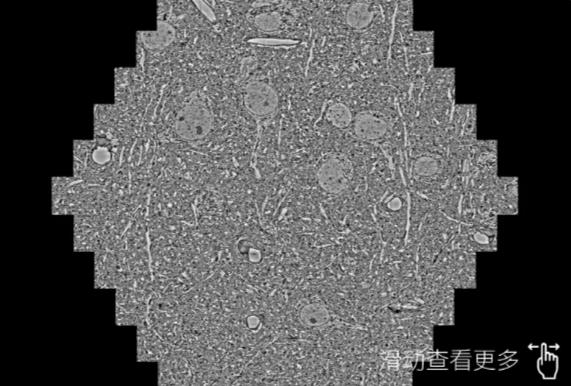

鼠脑切片。左图使用石嘴山蔡司石嘴山扫描电镜MultiSEM706对165μmx143pm面积区域成像,耗时仅需1.5秒。右图为鼠脑切片中30μm区域放大效果。样品由芝加哥大学B.Kasthuri提供。